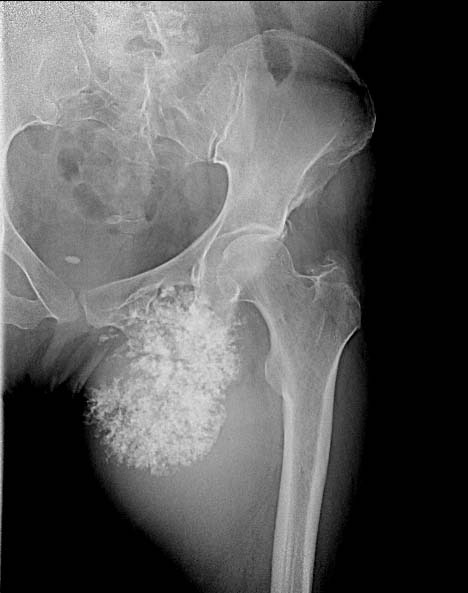

Фото: Rg при остеогенной саркоме бедренной кости

Фото: Рентгенограмма костей таза. Остеогенная саркома седалищной кости

Выполнение лишь одного метода визуализации не позволяет достаточно оценить данную патологию, например, рентгенография и компьютерная томография позволяют детально оценить изменение костной ткани, однако из-за специфики оптических свойств не дают полного представления о мягкотканных структурах и распространении по костномозговому каналу, что требует выполнения магнитно-резонансной томографии. Оценить распространение заболевания в целом позволяет применение различных методов радионуклидной диагностики – остеосцинтиграфии, ОФЭКТ и ПЭТ компьютерной томографии.